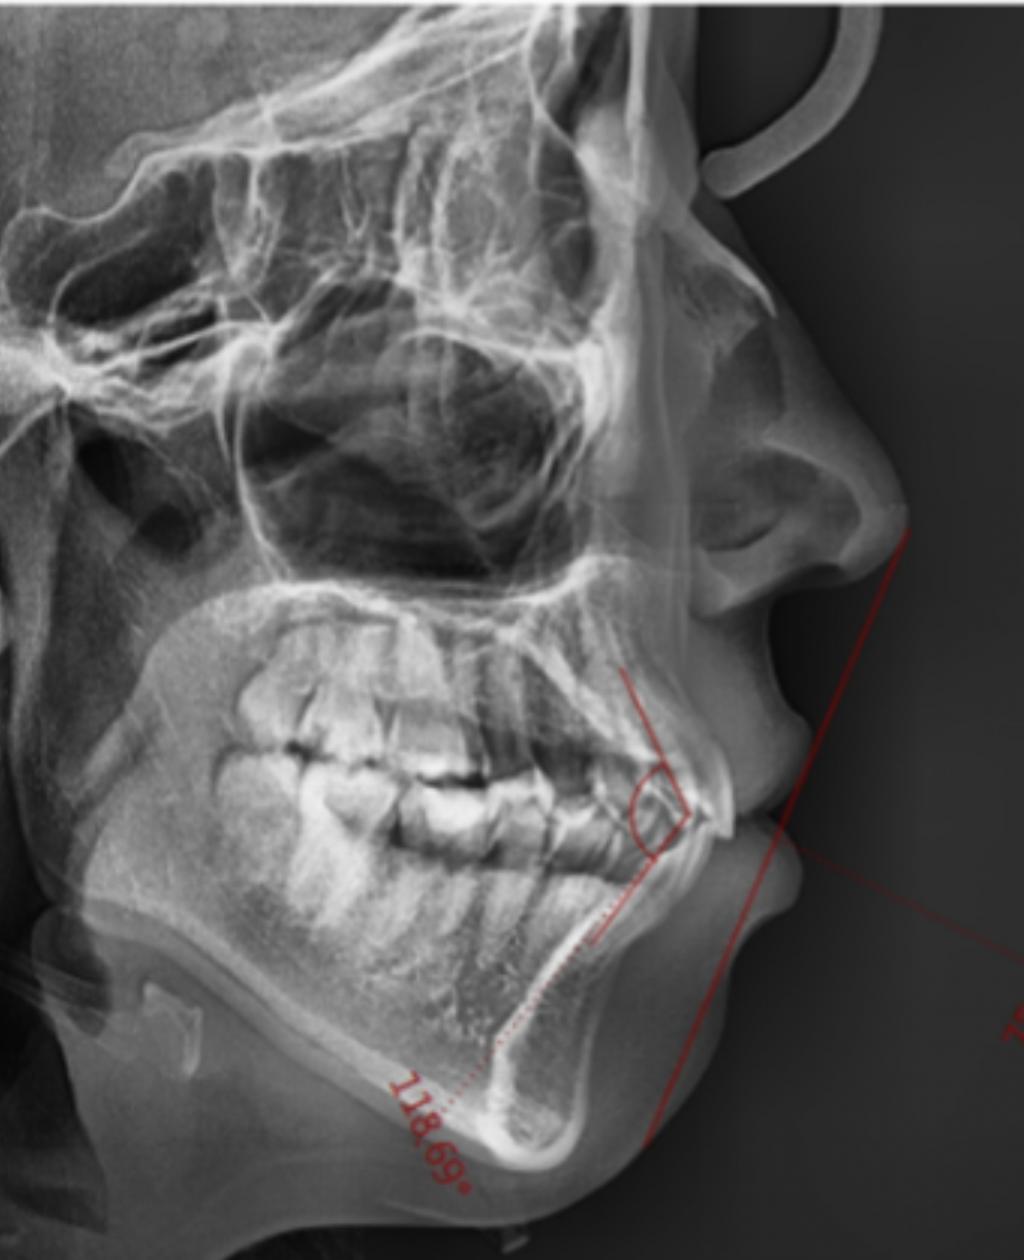

일단 저는 심하지는 않지만(?) 무턱이구요

제가 치아모양을 봤을땐 윗치아가 많이 튀어나온것 같진않은데

엑스레이사진으론 또 다르게 보이네요..

무턱이 교정되면 좋겠지만 옥니가 될까봐 걱정입니다

이게 제 옆모습 엑스레이 사진이구요 118.65도

입술쪽 직각선에는 75라고 써있었습니다